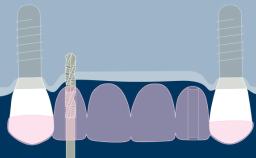

所有种植修复体的设计都应基于修复计划,并应满足所有相关的设计因素。大多数种植体固定义齿(或 FDP)的设计有许多共同点,以合理的设计遵循这些共同点很有帮助。第一要点是选择 FDP 的类型和方案。下一要点是选择固位方式,然后是考虑所需的外部和内部结构,以满足美观、功能和强度等因素。本模块将依次探讨每个设计要点。本网络学院设有单独且更详细的单元,将以现有模块为基础,阐述 FDP 修复材料、基台和种植体的选择。

- 外部设计